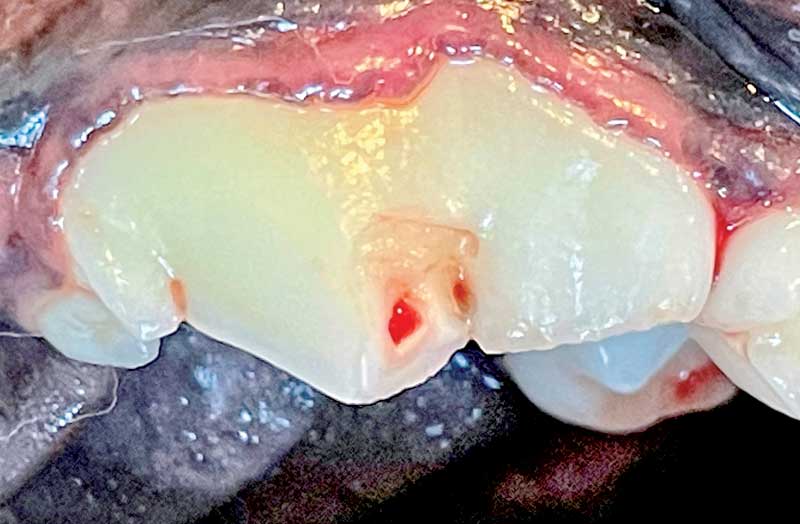

Figure 1: A complicated crown fracture of tooth 208. This tooth would likely be a good candidate for root canal therapy. Photos courtesy John Lewis

Tooth fractures can also fall into categories of "complicated crown fractures" (Figure 1) and "uncomplicated crown-root fractures." Complicated crown fractures are great candidates for the elegant, minimally invasive option of root canal therapy, as long as the canals are able to be cleaned and obturated (filled) appropriately to allow for a good prognosis. Uncomplicated crown-root fractures (Figure 3) may be able to be restored after raising a gingival flap to assess the extent of the subgingival fracture.